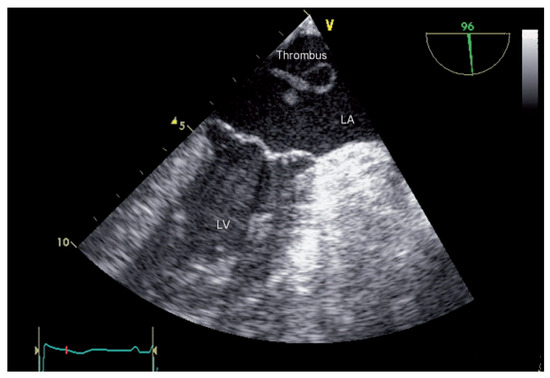

Der 70-jährige Patient wurde uns zugewiesen zur stationären kardialen Rehabilitation bei St. n. mechanischem Aortenklappenersatz wegen schwerer degenerativer Aortenstenose.[...]